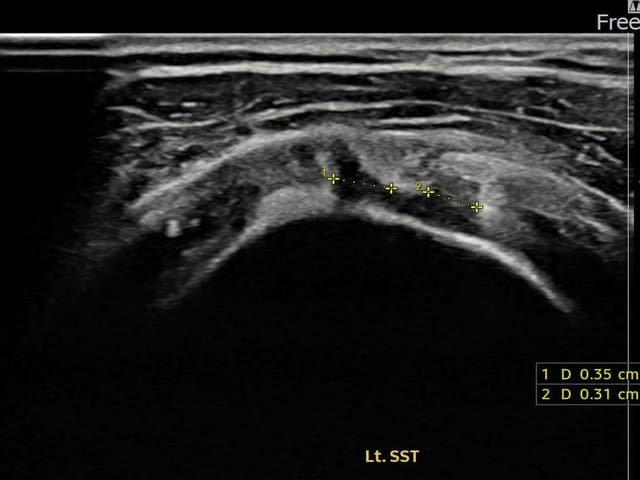

左侧 冈上肌腱 关节面侧部分撕裂

3.5mm × 3.1mm (부분파열)

左侧 冈上肌腱 附着部部分撕裂

5mm × 3mm (肌腱厚度约25%缺损)